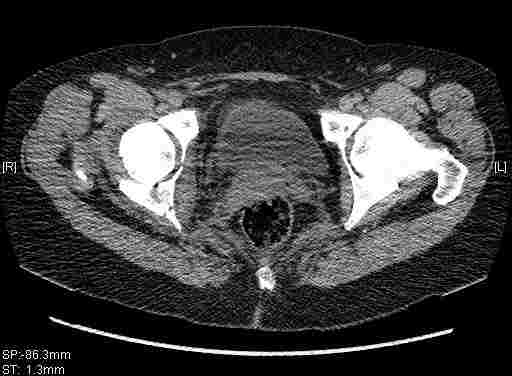

Остальные срезы.